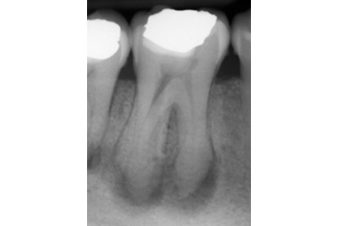

The extra root can be separate or partially fused with the other roots. Its morphology can vary from a short conical extension to one with a normal length (Figures 2 and 3). However, more often they are smaller than the other roots (Figure 4).

Radiographs and CBCT

It is important to assess radiographs carefully for the presence of extra roots.

In radix entomolaris, the disto-lingual root often lies on the same bucco-lingual plane as the main distal root.

This superimposition can ‘hide’ the root, making it difficult to identify. Therefore, a parallax radiograph (taken from a 30 degree mesial or distal angulation) is helpful.